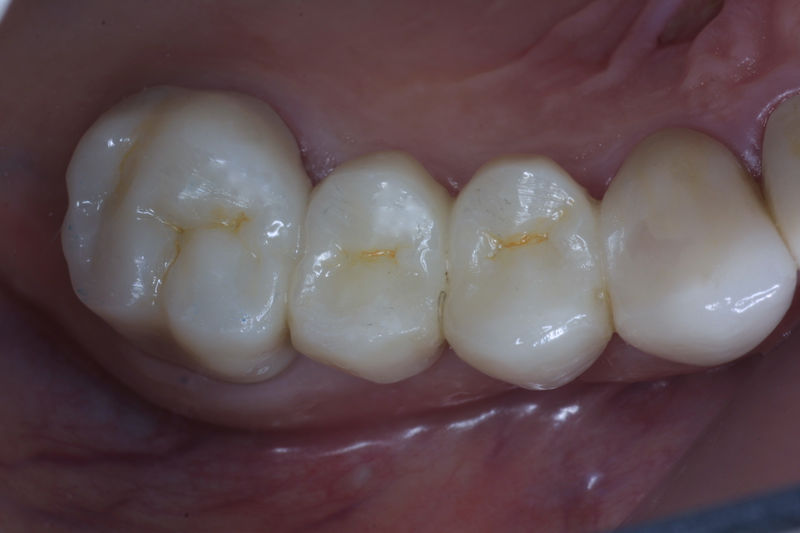

Restauraciones fabricadas en el laboratorio con materiales estéticos, los cuales cubren de manera parcial dientes posteriores. Se utilizan primariamente para restaurar dientes con caries, fracturas y/o defectos amplios. Para poder enviar el caso al laboratorio se toman impresiones utilizando materiales de impresión o técnicas modernas digitales.